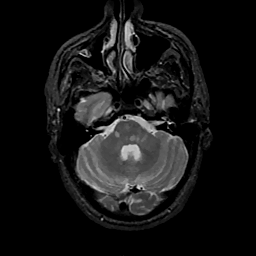

MR Study #11, May 5, 1991 -- Slice #12